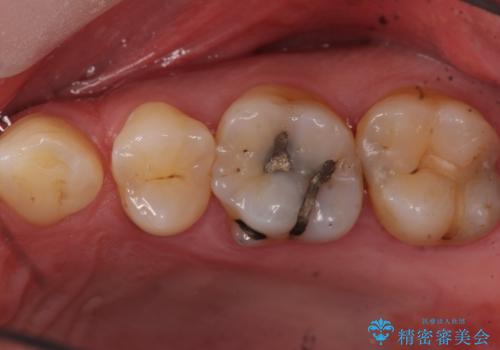

- 奥歯に物が詰まりやすいということが主訴で来院され、歯全体が虫歯になっていたので被せ物にて治療を行なった。

仮歯を装着した時点でものが挟まる症状は改善されました。

虫歯は綺麗に取り切れています。